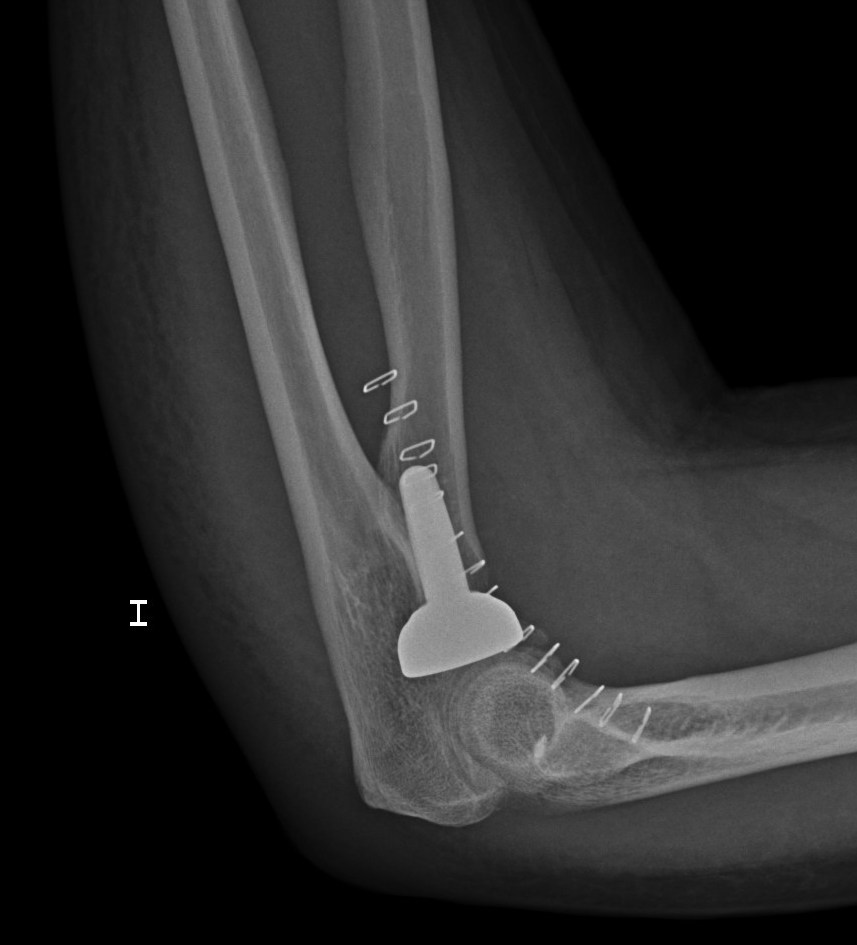

En la intervención se implantó un prótesis tal y como se aprecia en la radiografía: